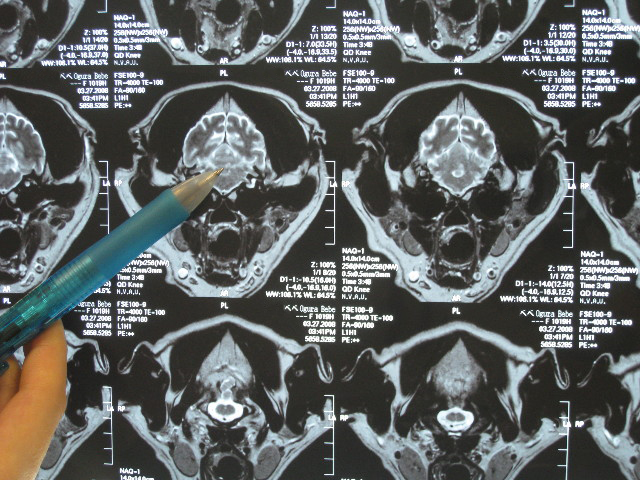

そしてMRIの現像を見せてもらいながら診察結果が告げられた。

【小脳梗塞】です。

脳は左右対称なので、対象ではない箇所があればそれが病変部分なんだって。

(たぶん仰向けに寝て、輪切りに撮ったところ)

梗塞が大きいと、白っぽい点ももっと大きいんだって。

(たぶん仰向けに寝てスライスするように撮ったところ)

こんな小さな病変で立てなくなっちゃうのね....。

でも軽度の梗塞で良かった!

●脳は左右対称である。対象でないところがあればそこが病変箇所である

●べべの病変は真ん中より1〜2ミリ左寄り。(この位置の病変だとマヒは左にでるはず?)